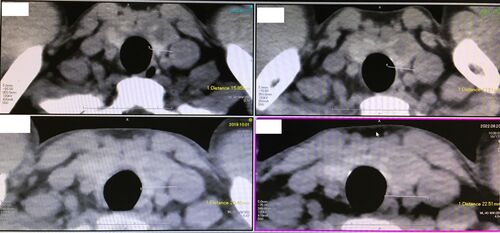

左肺上葉結節影同様、甲状腺左葉にも何かがあることは2016年から分かっていました。 とはいえ、甲状腺腫瘍ならよほど増大速度が速くない限りはしばらく経過観察でいいんじゃないかなあと高をくくっていました。 今年は消化器内科の先生の検査オーダーで撮影…